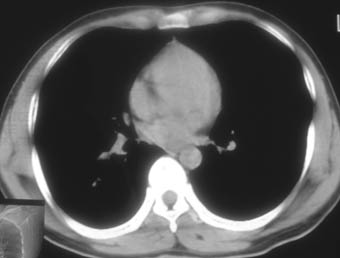

锁骨骨折复查,发现肺内高密度影,行ct检查。

男性,35岁,无任何感觉,无明显发热感冒病史。

右肺下叶背段斑片状阴影,边缘模糊,纵隔内未见肿大淋巴结,病人无发热及感冒史,要考虑浸润型肺结核,可结合ppd检查,或短期抗炎治疗复查。

右肺下叶背段长椭圆型病灶,边缘较规则,无明显分叶征、毛刺,远段未见阻塞征象,病灶较松散,纵隔窗明显小于肺窗,年龄35岁,支气管稍示变窄,纵隔内未见明显肿大淋巴结,这些都不支持肿瘤。病人无任何感觉,无明显发热感冒病史,首先考虑结核(也是结核好发部位),慢性炎症不能完全除外。